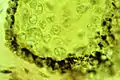

The microscope shows smoker's melanosis to be characterized by a melanin hyperpigmentation of the lower part of the oral epithelium, similar to sun-tanned skin. The hyperpigmentation consists of melanin granules which have the shape and colour of "coffea beans". They are produced by the dendritic, octopus-like melanocytes, seen between the epithelial cells situated closest to the epithelium/connective tissue border.[7]

Melanocytes in basal cells of a smoker's gum.

Melanocytes in basal cells of a smoker's gum. Melanin granules in the basal epithelium under light microscope